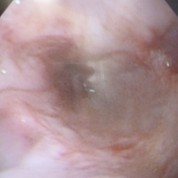

胃潰瘍

異物除去後